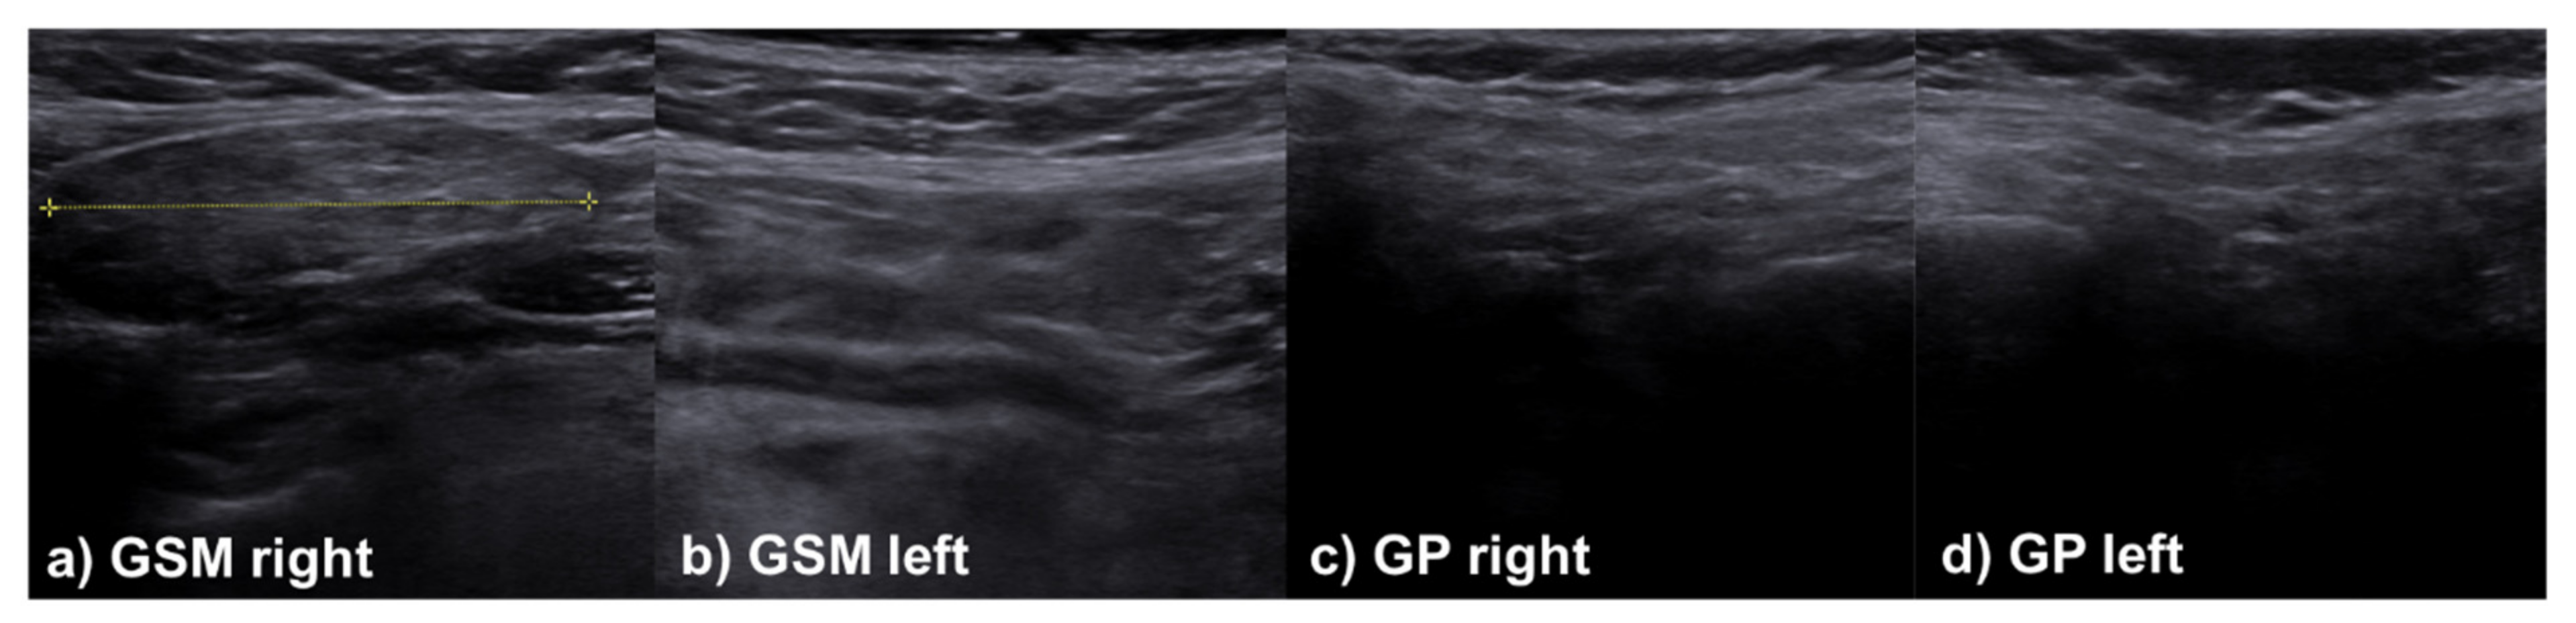

2.3. Sonographic Evaluation